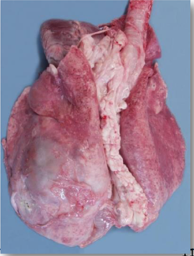

Pasteurella pnuemonia/septicaemia in a lamb

This a fibrinous pneumonia.

* Affected parts: usually the cranioventral lung regions. They feel consolidated/hard and not spongy.